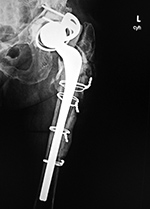

Revision total hip prosthesis |

Triflange acetabular component total hip revision arthroplasty with long femoral stem |

Triflange acetabular component total hip revision arthroplasty |

The revision prosthesis was placed because of an earlier periprosthetic fracture. There are two cable wires proximally and two cerclage wires distally. |

|

83 year-old woman |